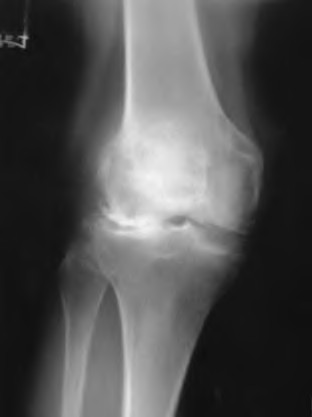

A 55-year-old male presents with isolated medial compartment osteoarthritis of the right knee. He is being evaluated for a medial unicompartmental knee arthroplasty (UKA). Which of the following physical examination or radiographic findings is an absolute contraindication to a medial UKA?